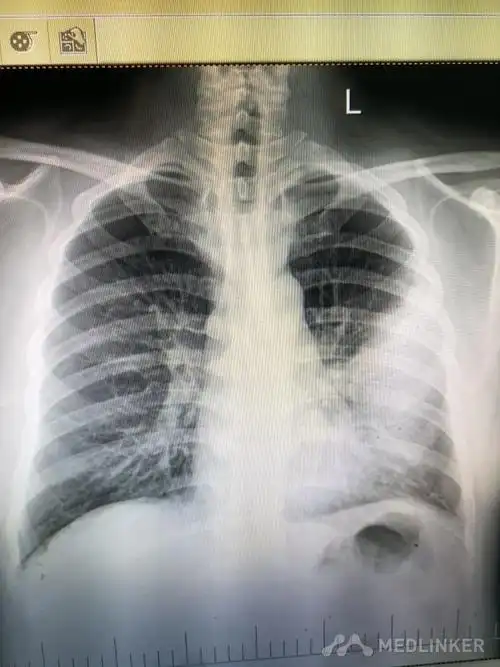

胸片如何看肺炎,这篇文章帮你立刻入门!

胸片如何看肺炎这篇文章帮你立刻入门